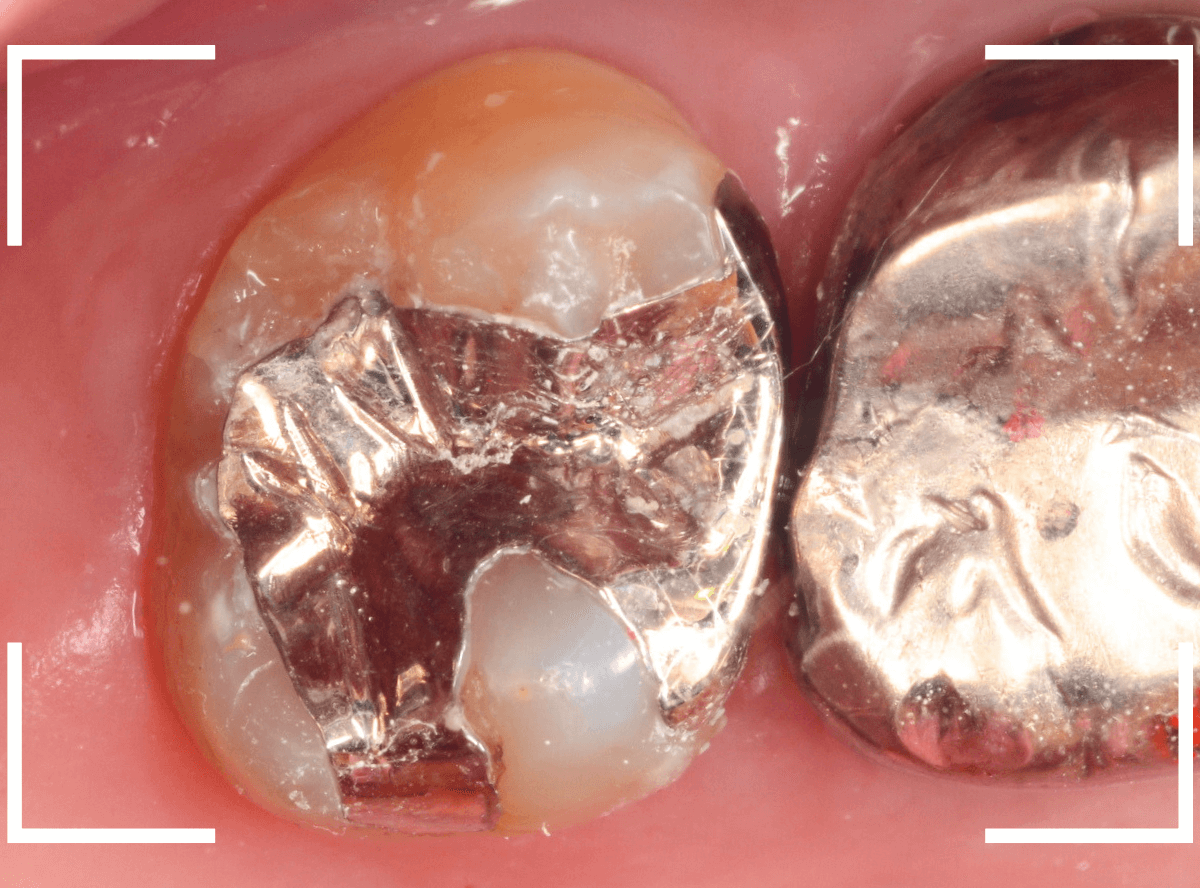

Case.18 2本に渡る大きな虫歯

「歯に大きな穴が開いていて痛い」という訴えで来院された患者さんです。

金属のつめものの脇に大きな穴が開いているのがわかります。

レントゲン写真で確認します。

赤い線が虫歯、青い線が神経です。

奥歯も神経に到達しそうな、大きな虫歯になっているのがわかります。

早めの治療が必要です。

まず、慎重に金属を除去します。

金属の下に敷いてあったセメントも劣化しているのが分かりますので、そちらも除去して調べます。

セメントも除去したところです。

両歯とも、とても大きな虫歯なのがわかります。

慎重に虫歯を除去したところで、染色液で虫歯が除去できたか調べます。

まだうっすら虫歯が残っているのが分かります。

ほぼ全ての虫歯を除去したところです。

どちらの歯も神経ギリギリまで虫歯が進行していました。

神経を保護するお薬をつめて、セメントでカバーしてしばらく経過観察します。

ほとんどの方は、症状ないですが、お痛みが出て続くようですと、改めて神経を除去する治療が必要になります。

ある程度進行した虫歯は、自然治癒しません。

痛むまで自己判断で経過観察せず、少しでも違和感を感じたら、早めに歯科医院でチェックしてもらうようにしましょう。